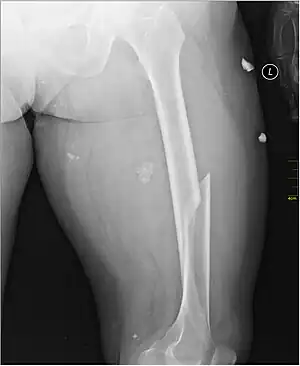

X-ray image of a femoral shaft fracture

Radiography

Anterior-posterior (AP) and lateral radiographs are typically obtained.[4]

In order to rule out other injuries, hip, pelvis, and knee radiographs are also obtained.[5]

Femoral shaft fractures

Femoral shaft fractures can be classified with the Winquist and Hansen classification, which is based on the amount of comminution.[6]

Intramedullary nailing

For femoral shaft fractures, reduction and intramedullary nailing is currently recommended.[13] The bone is re-aligned, then a metal rod is placed into the femoral bone marrow, and secured with nails at either end. This method offers less exposure, a 98–99% union rate, lower infection rates (1–2%) and less muscular scarring.[13][14][16]